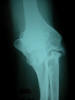

Prótesis completa de rodilla. Situación postquirúrgica.

Prótesis completa de rodilla. Situación postquirúrgica. Lateral.